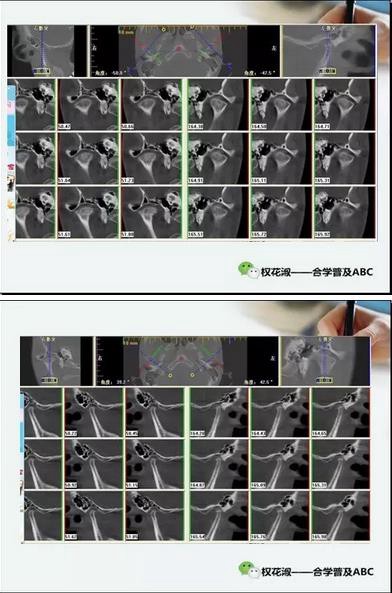

這是冠狀向和矢狀向的CT截圖,給大家一個粗略的概念,尤其是在看這個矢狀向的圖片,他們看他的關(guān)節(jié)已經(jīng)非常纖細單薄,髁突的髁頭已經(jīng)完全吸收了。回頭再看他第一張圖片,左側(cè)是一個口內(nèi)前牙的開合,右側(cè)是一個CT側(cè)面的截圖,從這個截圖當(dāng)中,大家可以進一步琢磨他下頜骨體的高陡,前后面高的變化,這些都提示我們他髁突已經(jīng)有明顯的吸收。